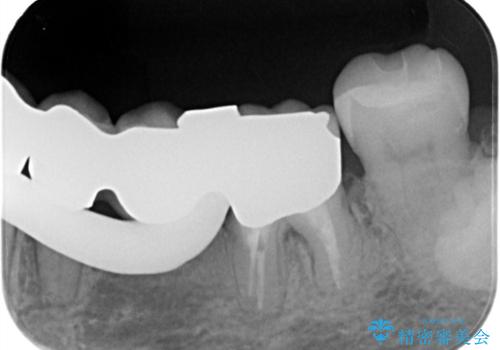

- 主訴:左下一番奥の銀の詰め物が外れてしまった。やり替えを機に綺麗なものを入れたい。

保険のメタルインレー脱離によるやり替え希望だったため、審美性・清掃性の良いセラミックインレーでのやり替えとなりました。

メタルインレー脱離後の窩洞をセラミックインレー窩洞に再形成し直し印象しています。遠心・舌側面のカリエスの除去、残存歯質の破折リスクを考えアンレー形態となりました。

アンレー装着時にはラバーダム防湿を行っています。